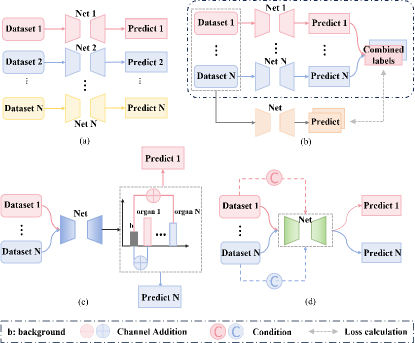

A straightforward strategy to use these partially labeled datasets is to train a segmentation model independently for each dataset, and then combine the outputs of these models to obtain the final multi-organ segmentation result. This approach is known as multiple networks and is shown in Fig. 1 (a). Although simple, it has several obvious shortcomings: first, both the training and inference processes are time-consuming, while also necessitating substantial memory allocation for storing multiple models; second, during the inference stage, a challenge arises when integrating the outputs of individual models due to the voxel prediction conflicts, i.e., the prediction results for the same voxel may be not consistent from different models; and lastly, if datasets are trained independently with segmentation models, the prior information (such as size and position) contained between organs labeled in different datasets will not be effectively utilized, which makes it difficult to achieve optimal segmentation results [4].

The prevailing approach is to concurrently train a unified segmentation model using multiple datasets. Existing methods for training such models can be classified into three categories: Pseudo-Labeling: As shown in Fig. 1 (b), this approach initially trains models on individual datasets to segment specific organs, and then uses these models to generate pseudo labels for corresponding organs on other datasets. These combined labels are then used to train a unified multi-organ segmentation model. Research in this area focuses on enhancing the quality of pseudo labels [5, 6, 7]. Channel Adjustment: Illustrated in Fig. 1 (c) , this method employs a multi-channel output model. Due to the lack of labels for all channels, unlabeled channels are treated as background during loss calculation, which is called Target Adaptive Loss (TAL) [8]. Shi et al. [9] introduced additional marginal loss from other datasets to improve segmentation accuracy. Liu et al. [4] initially trained a model with TAL and then iteratively refined it using self-training with pseudo labels. Conditional Information Guidance: Depicted in Fig. 1 (d), this method integrates conditional information into the segmentation model, allowing the model to produce organ-specific segmentation result based on this information during inference. This conditional information is typically embedded into the network’s final layers, guiding the network’s output to correspond to the given condition [10, 11, 12, 13].